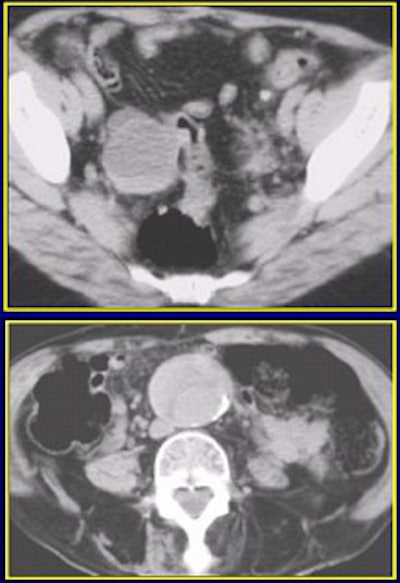

On 120 mAs (above) and 240 mAs (below), an extraurinary diagnosis of right hemorrhagic ovarian cysts and abdominal aortic aneurysm. Images courtesy of Dr. James Bell.